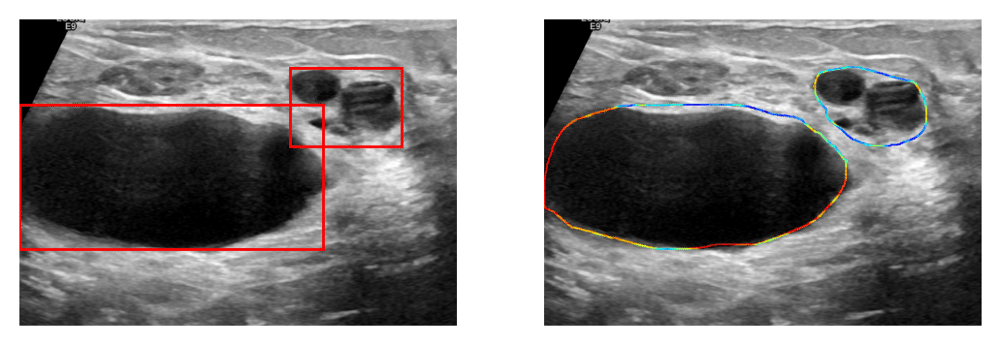

Visualizations help highlight the tumor location and give us the intensity of the tumor at each point in AOI (Area of Interest).

The app takes the image and mask generated from a model as input and gives us the bounded box, mask outline, and heatmap.

Then, the image and contours are sent to _bbAndMask and _heatmap functions to get a bounded box, mask outline, and heatmap.

The bounded box and mask outline are shown in a single figure with two axes.

Bounded Box

Mask Outline

We successfully created a Streamlit app that takes the inputs — image, and mask by browsing files on the computer, and shows the bounded box and mask outline on the image and a heat map with an interactive slider to get a sense of the tumor intensity.